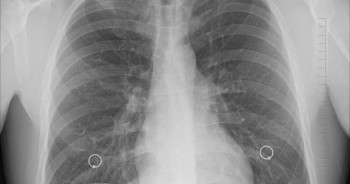

В России проводится Неделя сохранения здоровья легких

Жизнь всего человеческого тела и каждой его клетки зависит от наличия кислорода.

Жизнь всего человеческого тела и каждой его клетки зависит от наличия кислорода. И единственный орган нашего тела, который способен получить его – это легкие.